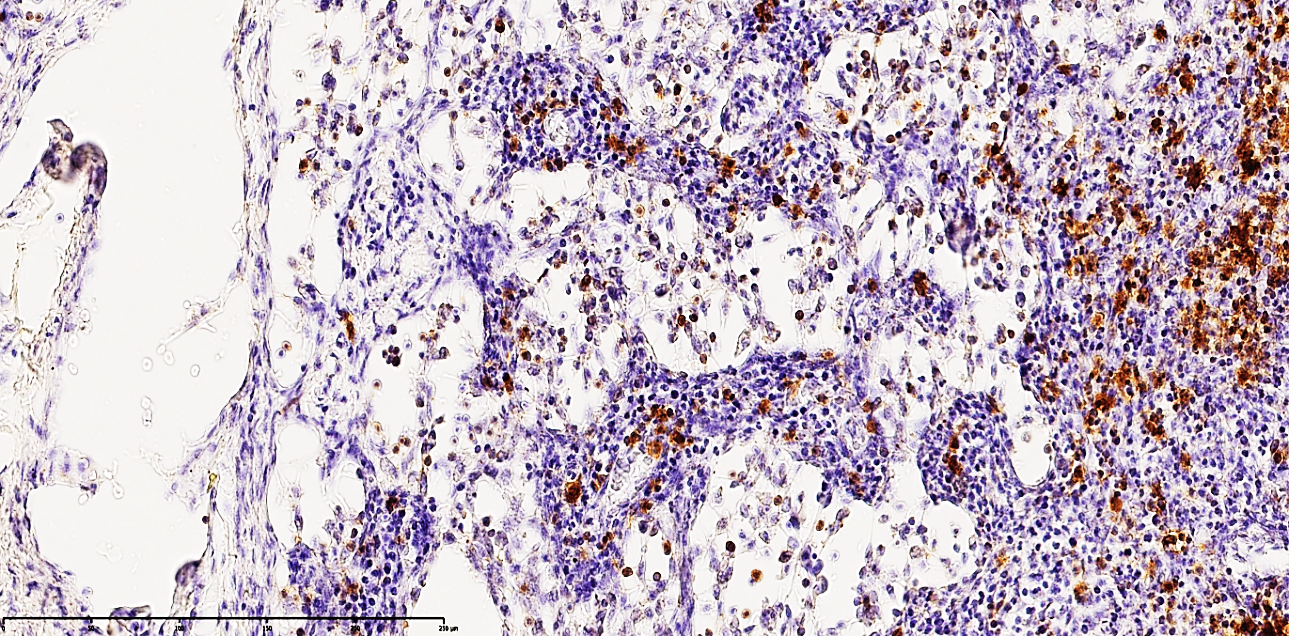

In the hyperacute phase of purulent peritonitis (days 1–3), a massive mobilization of lymphocytes toward inflammatory foci leads to a critical reduction of T and B cells within the regional lymph nodes.Key Findings:1. Follicular Collapse: Germinal centers in the marginal zones of cortical follicles showed significant atrophy and structural breakdown.2. T-Cell Deficit: Paracortical zones exhibited a sharp decline in CD3+ and CD4+ lymphocytes. Of the 33 patients studied in depth: 63.63% (n=21) showed a low positive reaction, while 36.36% showed a completely negative reaction.3. Reticulocytosis and Macrophage Infiltration: The paracortical areas showed increased reticular structures and an influx of large CD68+ macrophages. These cells were characterized by dark basophilic cytoplasmic inclusions.4. Proliferative Shift: While mature lymphocytes were depleted, the presence of small CD3+ and CD4+ positive cells (lymphoblasts) suggests a desperate attempt at proliferative activity despite the overarching state of immunodeficiency. | Figure 1. Mesenteric lymph node from a 21-year-old patient with acute secondary peritonitis. Immunohistochemical staining reveals a moderately low positive expression of the CD68 3 marker. Note the scattered distribution of macrophages and the depleted population of T-lymphocytes within the paracortical zones, visualized by the yellow-brown DAB (Diaminobenzidine) chromogen reaction. Counterstained with hematoxylin. Magnification: 10х10 |

The CD68 marker, primarily an adhesive membrane protein of macrophages, identifies these cells as they migrate from affected tissues through lymphatic vessels into the regional lymph nodes. In this study, out of 33 patients, 27 (81.81%) exhibited moderate positive expression, while 6 (18.18%) showed low positive reactions. These shifts confirm that a critical deficiency of immunocompetent cells within the lymph node triggers a compensatory increase in the phagocytic activity of macrophages. The observed enlargement of CD68-positive macrophages to giant proportions, characterized by dense, homogeneous, dark basophilic cytoplasmic inclusions, indicates an advanced state of phagocytosis following the ingestion of tissue debris. This phenomenon underscores that during the initial 1–3 days of acute peritonitis, a forced lymphatic drainage process occurs alongside the massive mobilization of lymphocytes toward inflammatory foci.Furthermore, a massive proliferation of CD68+ macrophages coupled with a profound depletion of lymphocytes is observed within the cortical and medullary layers, the paracortical zones, and the lymphoid follicles. This not only signifies the progression of secondary immunodeficiency but also reflects heightened proliferative activity of reticulocytes and an increase in fibroblasts and histiocytes. The chaotic formation of numerous reticular processes within the medullary cords, arising in response to the sharp decline in lymphocytes, indicates an intensifying process of massive delimphatization. Simultaneously, the accumulation of phagocytically active macrophages represents an attempt to fill the structural voids caused by nodal collapse, which is further exacerbated by the development of interstitial edema. The fraying and plasmatic swelling of the reticular fibers forming the medullary cords, combined with excessive fibroblast proliferation, allow for the prediction of burgeoning lymphoreticulosis and lymphoreticulosclerosis within the medullary substance.The drastic reduction of CD20+ B-lymphocytes, the delimphatization of lymphoid follicles in the cortical zone, and the predominant accumulation of macrophages within secondary follicles collectively indicate the development of focal lymphadenitis, a finding corroborated by neutrophil accumulation along the marginal surfaces of the follicles. In the paracortical zones, the residual small lymphocytes and lymphoblasts are found to have undergone incomplete apoptosis. Numerous reticulocytes and phagocytically active CD-receptor macrophages are identified surrounding these apoptotic and necrobiotic cells. Among the 33 cases studied, 11 patients showed a moderately low positive reaction for the CD20 marker, while 21 patients exhibited a completely negative reaction, further confirming the manifestation of severe secondary immunodeficiency as detailed above.